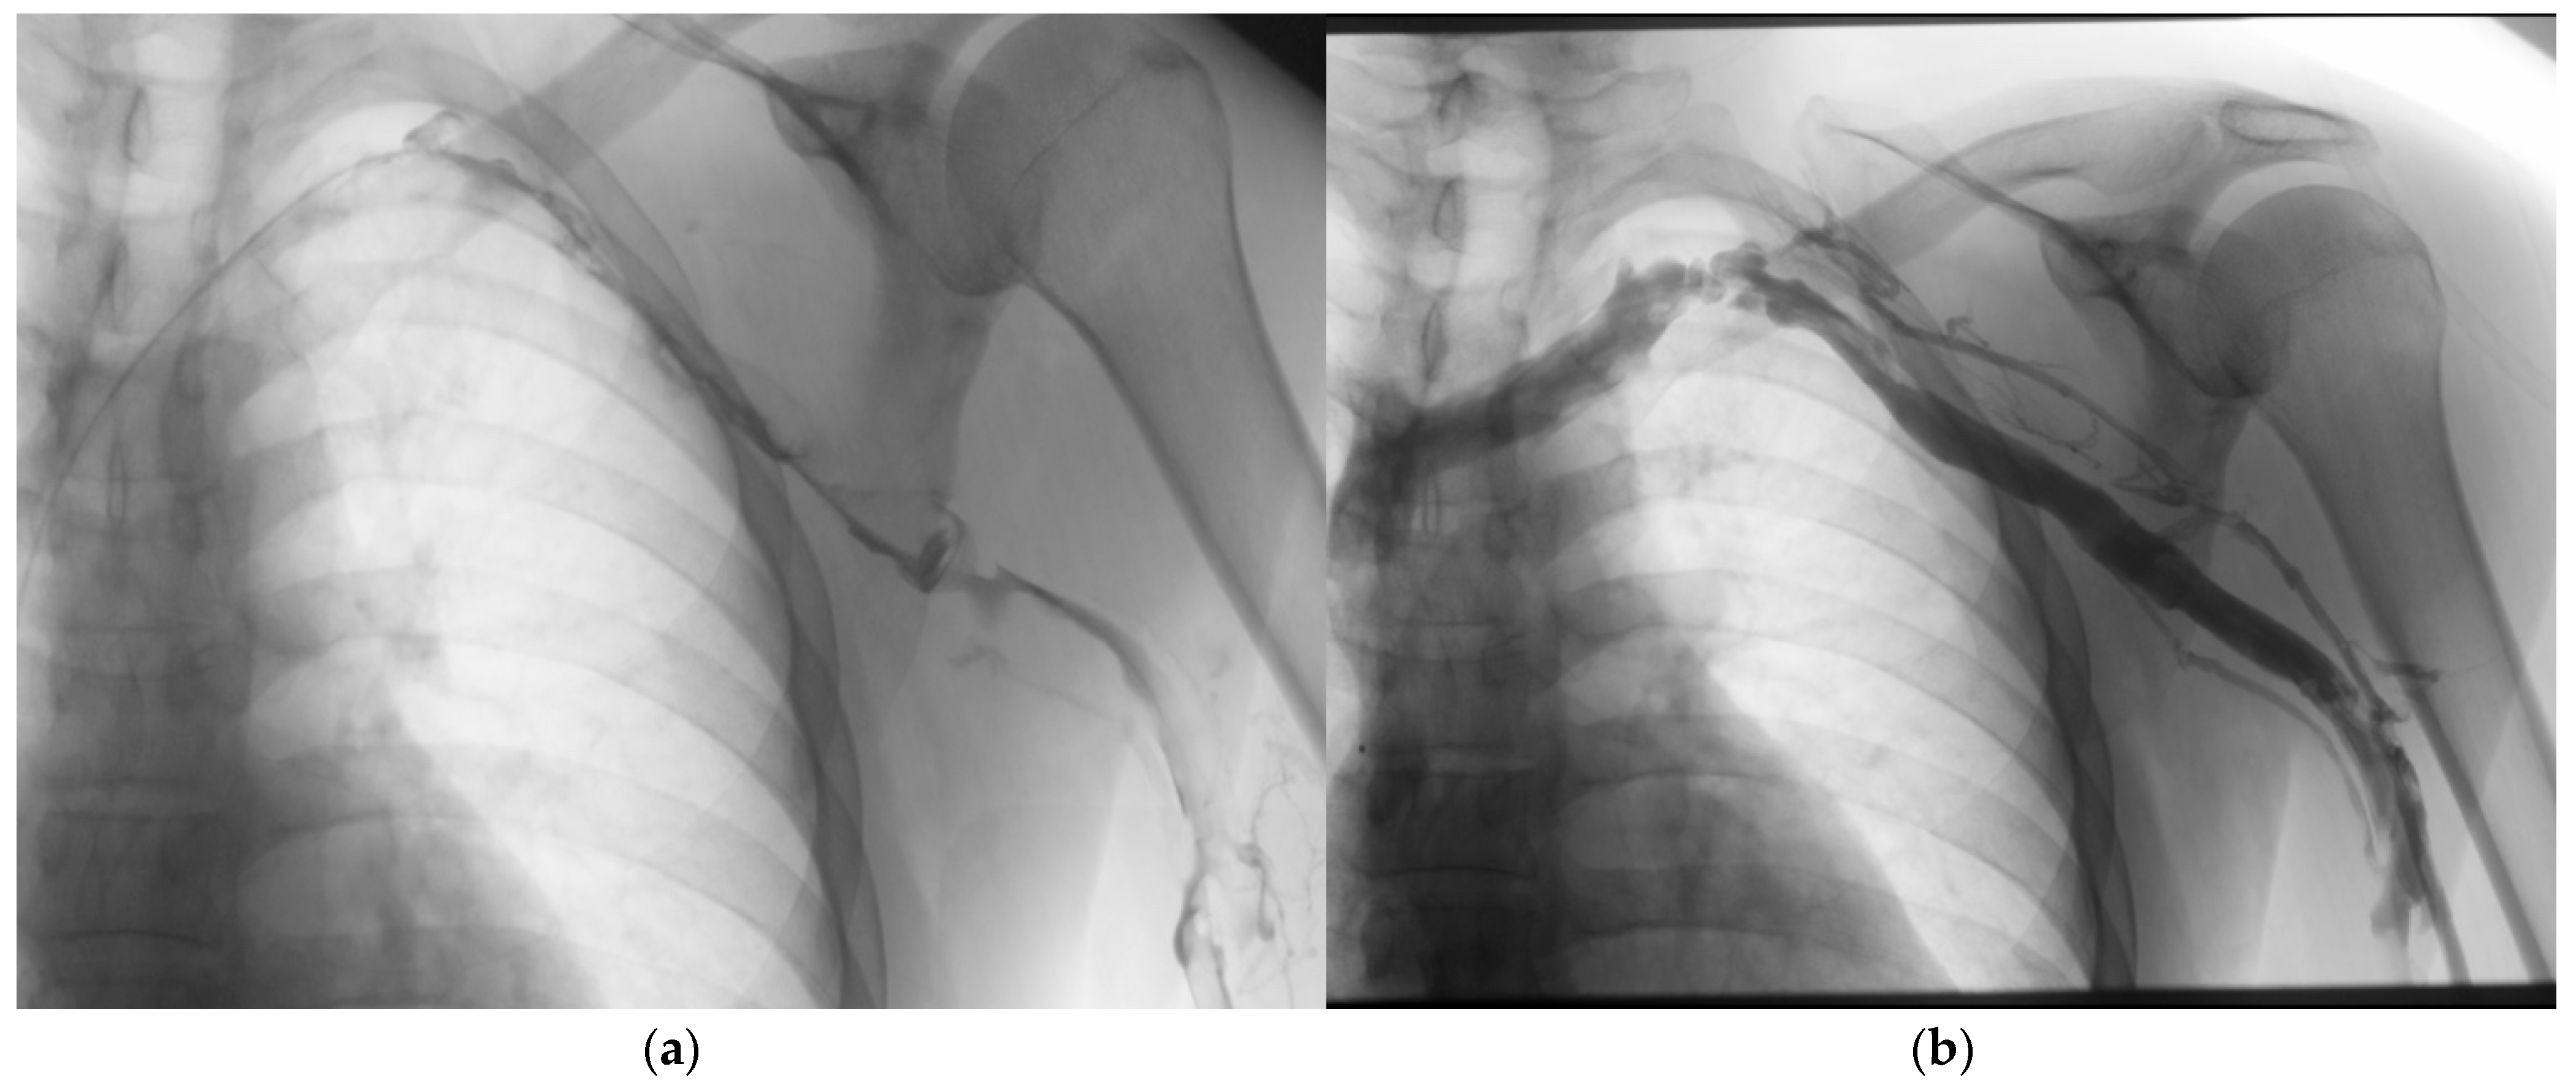

4.1. Catheter-Directed Thrombolysis

4.1.2. Adjunctive Techniques